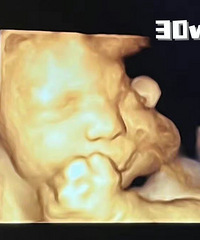

35,生下我的试管宝宝

今天是宝宝出生的第五天啦,来发帖记录一下生产过程,免得时间一过就忘记了。我是试管怀的,过程很不容易,之前有分享过试管帖子,这里就不啰嗦啦,这篇帖子就说生娃。我的预产期本来是1月19日,本来还想着到预产期生的话还可以蹭公司的春节假期,多休10天还是好安逸,结果……我说了不算,娃着急出来了。宝宝来镇楼!